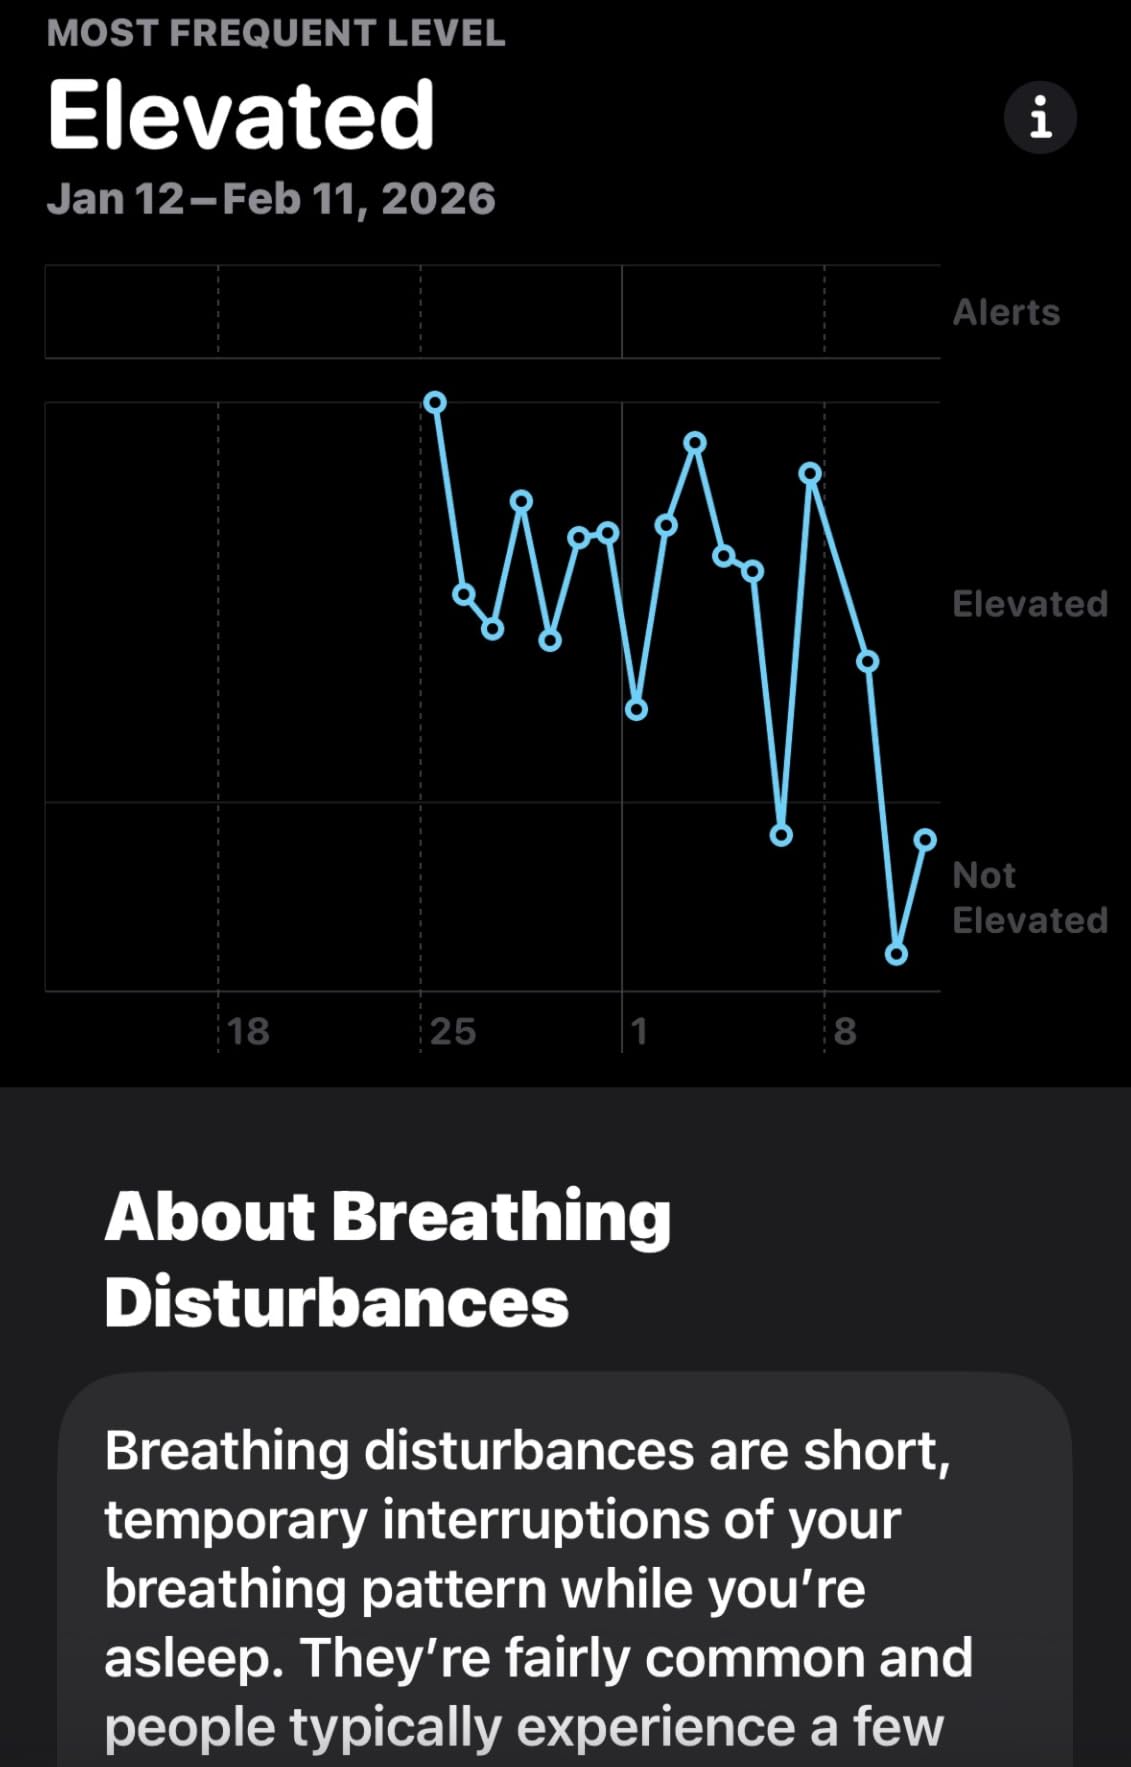

Sleep Apnea Warning: When to See a Doctor

Snoring can be a symptom of obstructive sleep apnea, a serious condition where your breathing repeatedly stops and starts during sleep. If you experience any of these warning signs, consult a healthcare professional before trying anti-snoring devices:

Gasping or choking during sleep, excessive daytime sleepiness despite adequate sleep time, morning headaches, difficulty concentrating, or a partner observing that you stop breathing during sleep. Sleep apnea requires medical diagnosis and may need treatment beyond over-the-counter devices.

Even if you don't have sleep apnea symptoms, if snoring persists despite trying multiple devices, a sleep study can identify underlying causes and guide more effective treatment options.